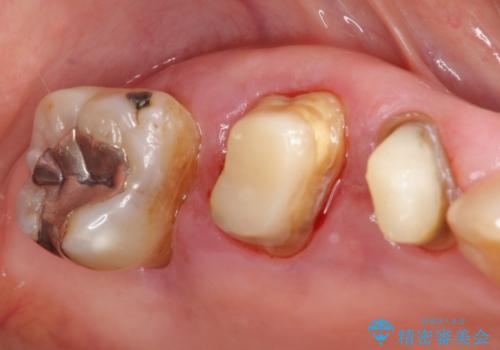

- 歯ぐきからの出血と腫れを主訴に来院された患者様です。

プラークコントロールが非常に悪く、全顎的な歯周病に罹患していました。

「抜歯したくない、インプラントは嫌」という患者様のご希望とご年齢を考慮し、可及的な骨外科処置や根分割術によりできるだけ今ある歯を残す治療方針をたてました。

被せ物の種類:メタルボンドクラウン エコノミー